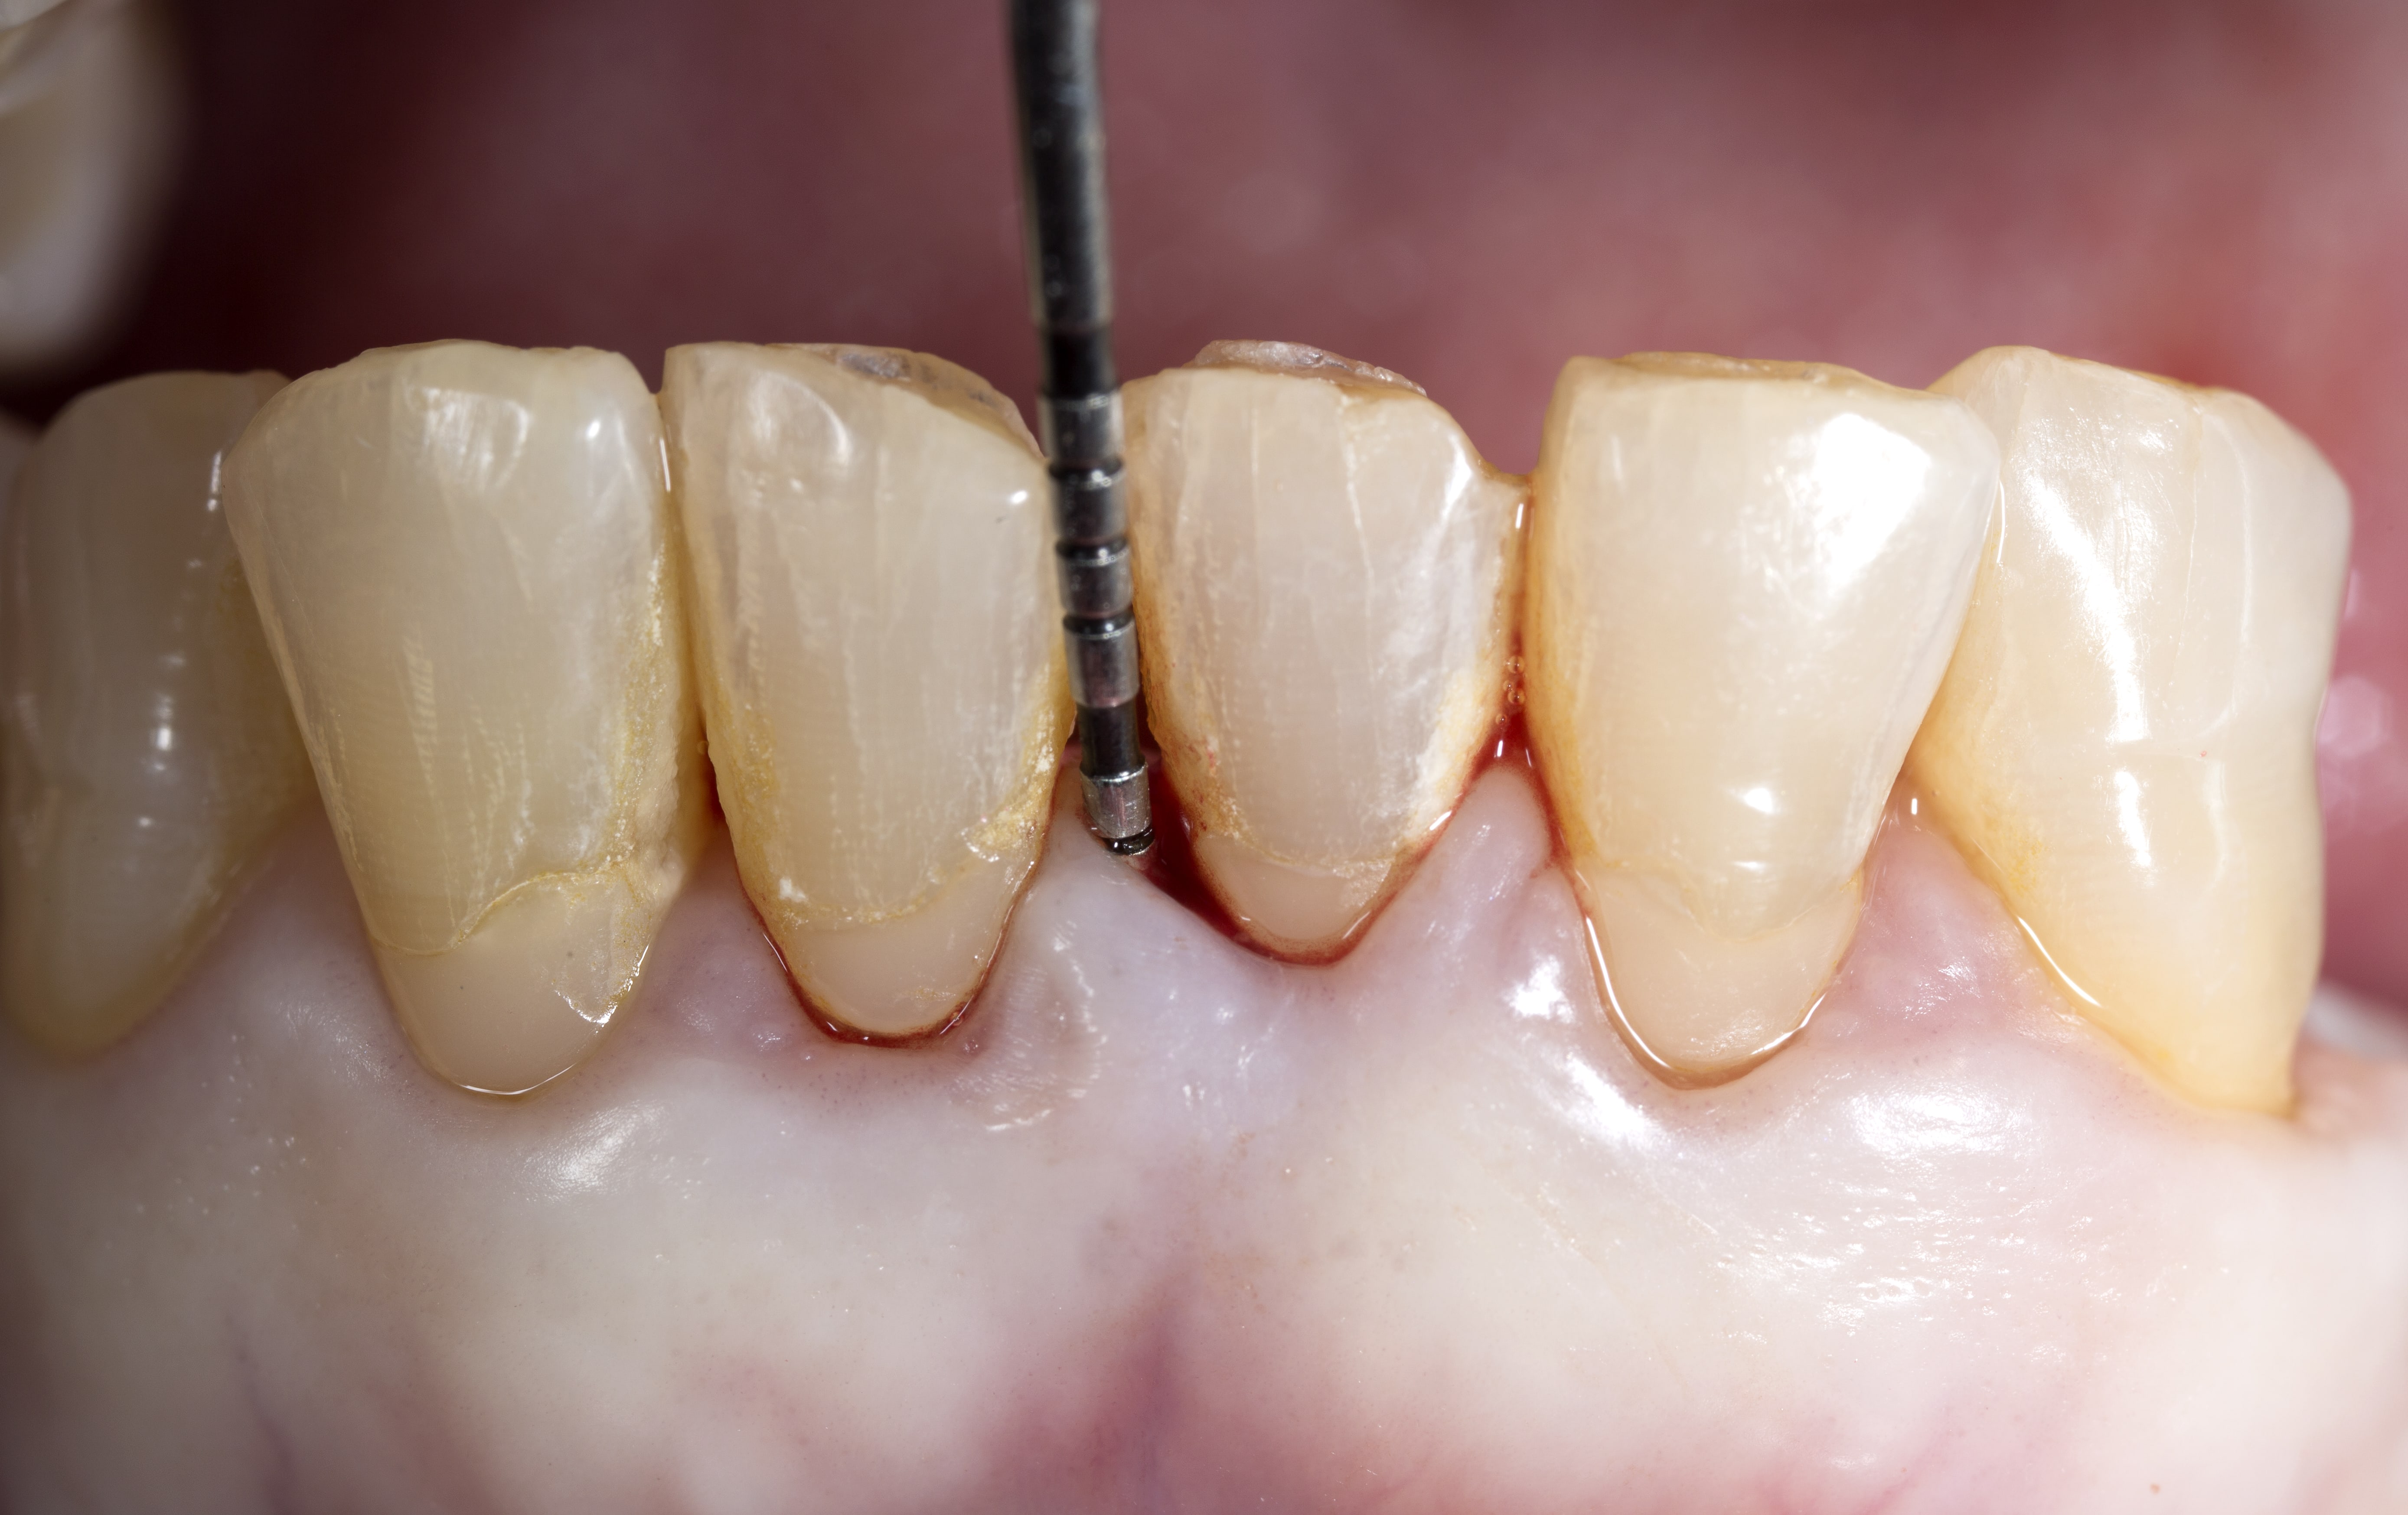

Periodontal Disease Probes . This randomized controlled trial compared. Clinical periodontal probing assessment methods, including probing pocket depth (ppd), bleeding on probing (bop), clinical. Periodontal probes are the main instruments that are used to assess the status of the periodontium, either for screening purposes or to evaluate periodontal changes. Periodontal probes are the main instruments that are used to assess the status of the periodontium, either for screening purposes or to evaluate. Periodontal diseases have long been diagnosed based on various factors such as bleeding on probing, probing depth, clinical. Electronic probes aim to objectify and facilitate the diagnostic process. A periodontal probe is a dental instrument used to measure the depth of the spaces, known as sulci or pockets, between your teeth and gums.

Periodontal probes are the main instruments that are used to assess the status of the periodontium, either for screening purposes or to evaluate. This randomized controlled trial compared. Electronic probes aim to objectify and facilitate the diagnostic process. Clinical periodontal probing assessment methods, including probing pocket depth (ppd), bleeding on probing (bop), clinical. A periodontal probe is a dental instrument used to measure the depth of the spaces, known as sulci or pockets, between your teeth and gums. Periodontal probes are the main instruments that are used to assess the status of the periodontium, either for screening purposes or to evaluate periodontal changes. Periodontal diseases have long been diagnosed based on various factors such as bleeding on probing, probing depth, clinical.

Periodontal Disease Probes Periodontal diseases have long been diagnosed based on various factors such as bleeding on probing, probing depth, clinical. Periodontal diseases have long been diagnosed based on various factors such as bleeding on probing, probing depth, clinical. Periodontal probes are the main instruments that are used to assess the status of the periodontium, either for screening purposes or to evaluate periodontal changes. Electronic probes aim to objectify and facilitate the diagnostic process. Clinical periodontal probing assessment methods, including probing pocket depth (ppd), bleeding on probing (bop), clinical. This randomized controlled trial compared. A periodontal probe is a dental instrument used to measure the depth of the spaces, known as sulci or pockets, between your teeth and gums. Periodontal probes are the main instruments that are used to assess the status of the periodontium, either for screening purposes or to evaluate.